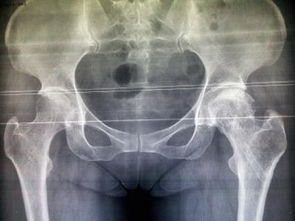

股骨頭壞死即股骨頭缺血性壞死,又稱無菌性股骨頭壞死。其癥狀是由于不同致病原因破壞了股骨頭的血液供應(yīng),因骨缺血而發(fā)生股骨頭骨質(zhì)壞死。 分型:股骨頭壞死的不同類型及壞死范圍和部位對治療方法的選擇起著重要的作用,因此我們結(jié)合X片、ECT及手術(shù)所見把股骨頭壞死分為以下四型、三級。